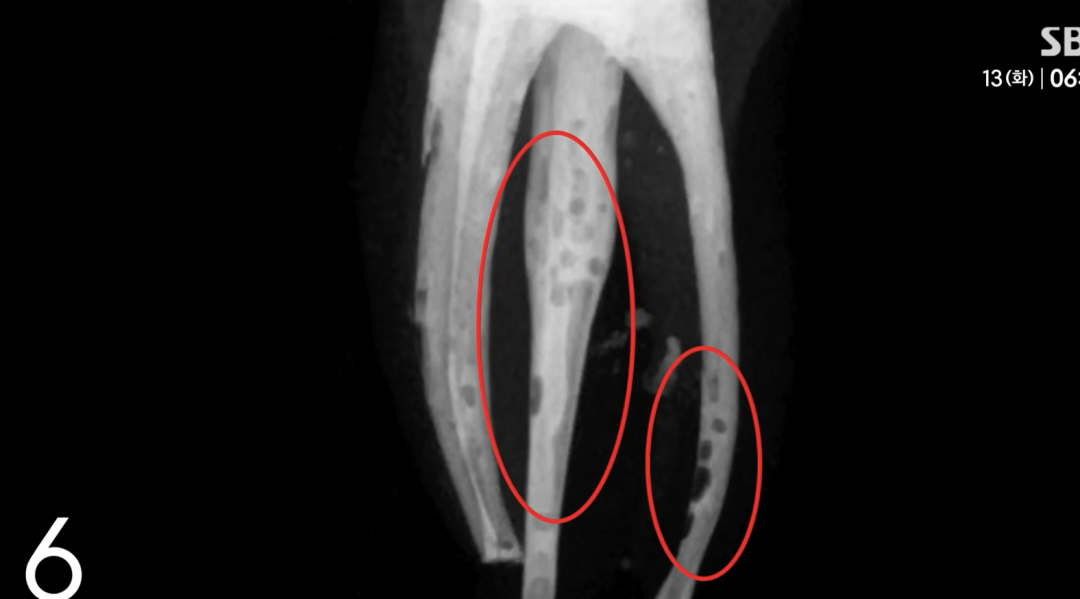

原始照片的显示,由于填充物不足,患者的牙根部位留有缝隙和气泡,这些是治疗不完善的表现。

而学生提交给学院的照片却经过精心处理,所有问题都被PS给“修复”了,营造了完美填充、治疗成功的假象。

(x光片照片ps前后对比)